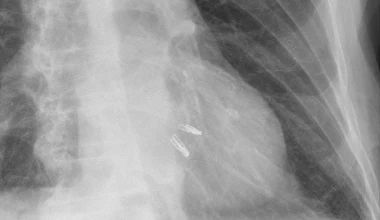

Zdjęcie RTG przedstawiające dwa urządzenia MitraClips umieszczone w sercu /Fot. Hellerhoff

GeekExtra

Pierwszy taki zabieg w Instytucie Kardiologii w Warszawie